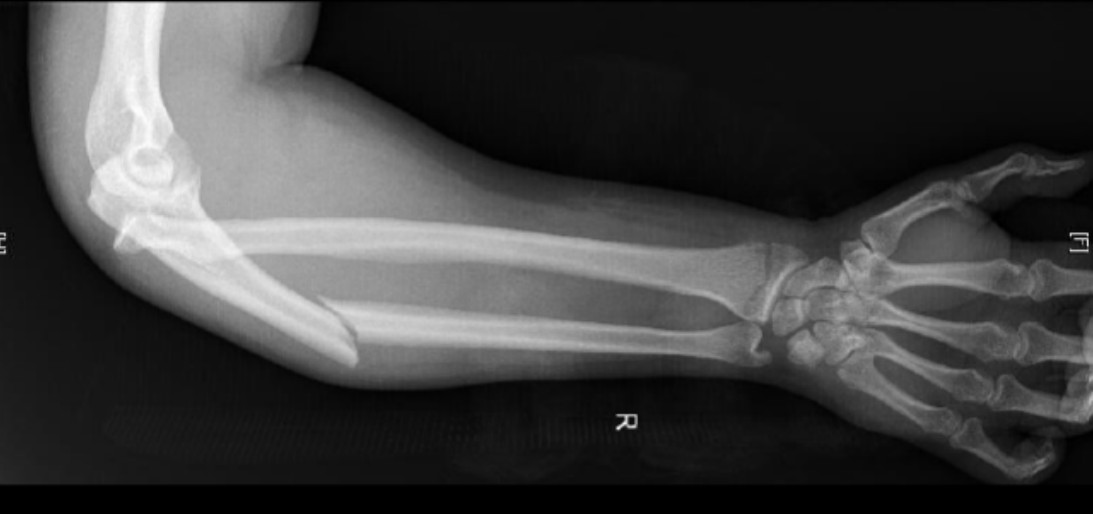

Arm injury

A 35-year-old man presents with a painful right arm after a fall from his jet ski 1 hour prior to …

A 35-year-old man presents with a painful right arm after falling from a jet ski.